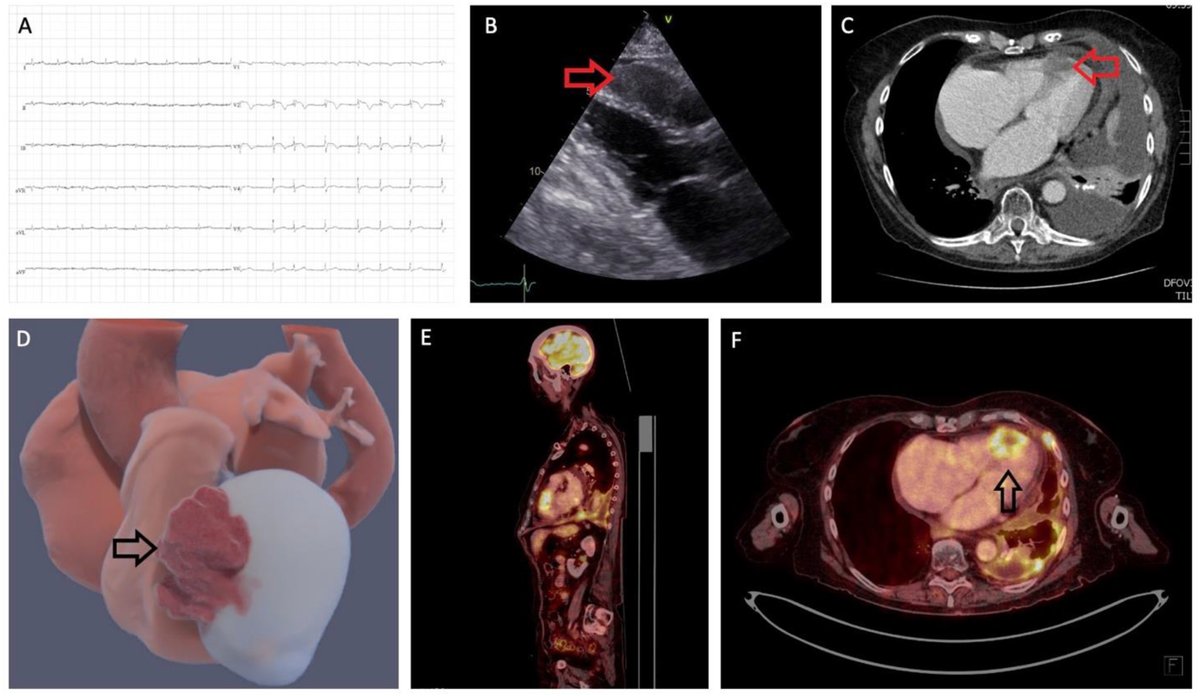

Can multimodality imaging help diagnose rare #cardiactumors? Check the #ImageOfTheMonth featuring a case of giant cavernous #hemangioma in the RV, diagnosed using ECHO, CCT, and CMR https://t.co/9SiTuJE22G @hjc_ed @zhengliumdpumc #echoFirst #yesCCT #whyCMR #Cardiacimaging.